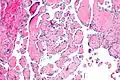

Intravascular papillary endothelial hyperplasia is a rare, benign tumor. It may mimic an angiosarcoma, with lesions that are red or purplish 5-mm to 5-cm papules and deep nodules on the head, neck, or upper extremities.[1][2]: 592

Histopathology Images